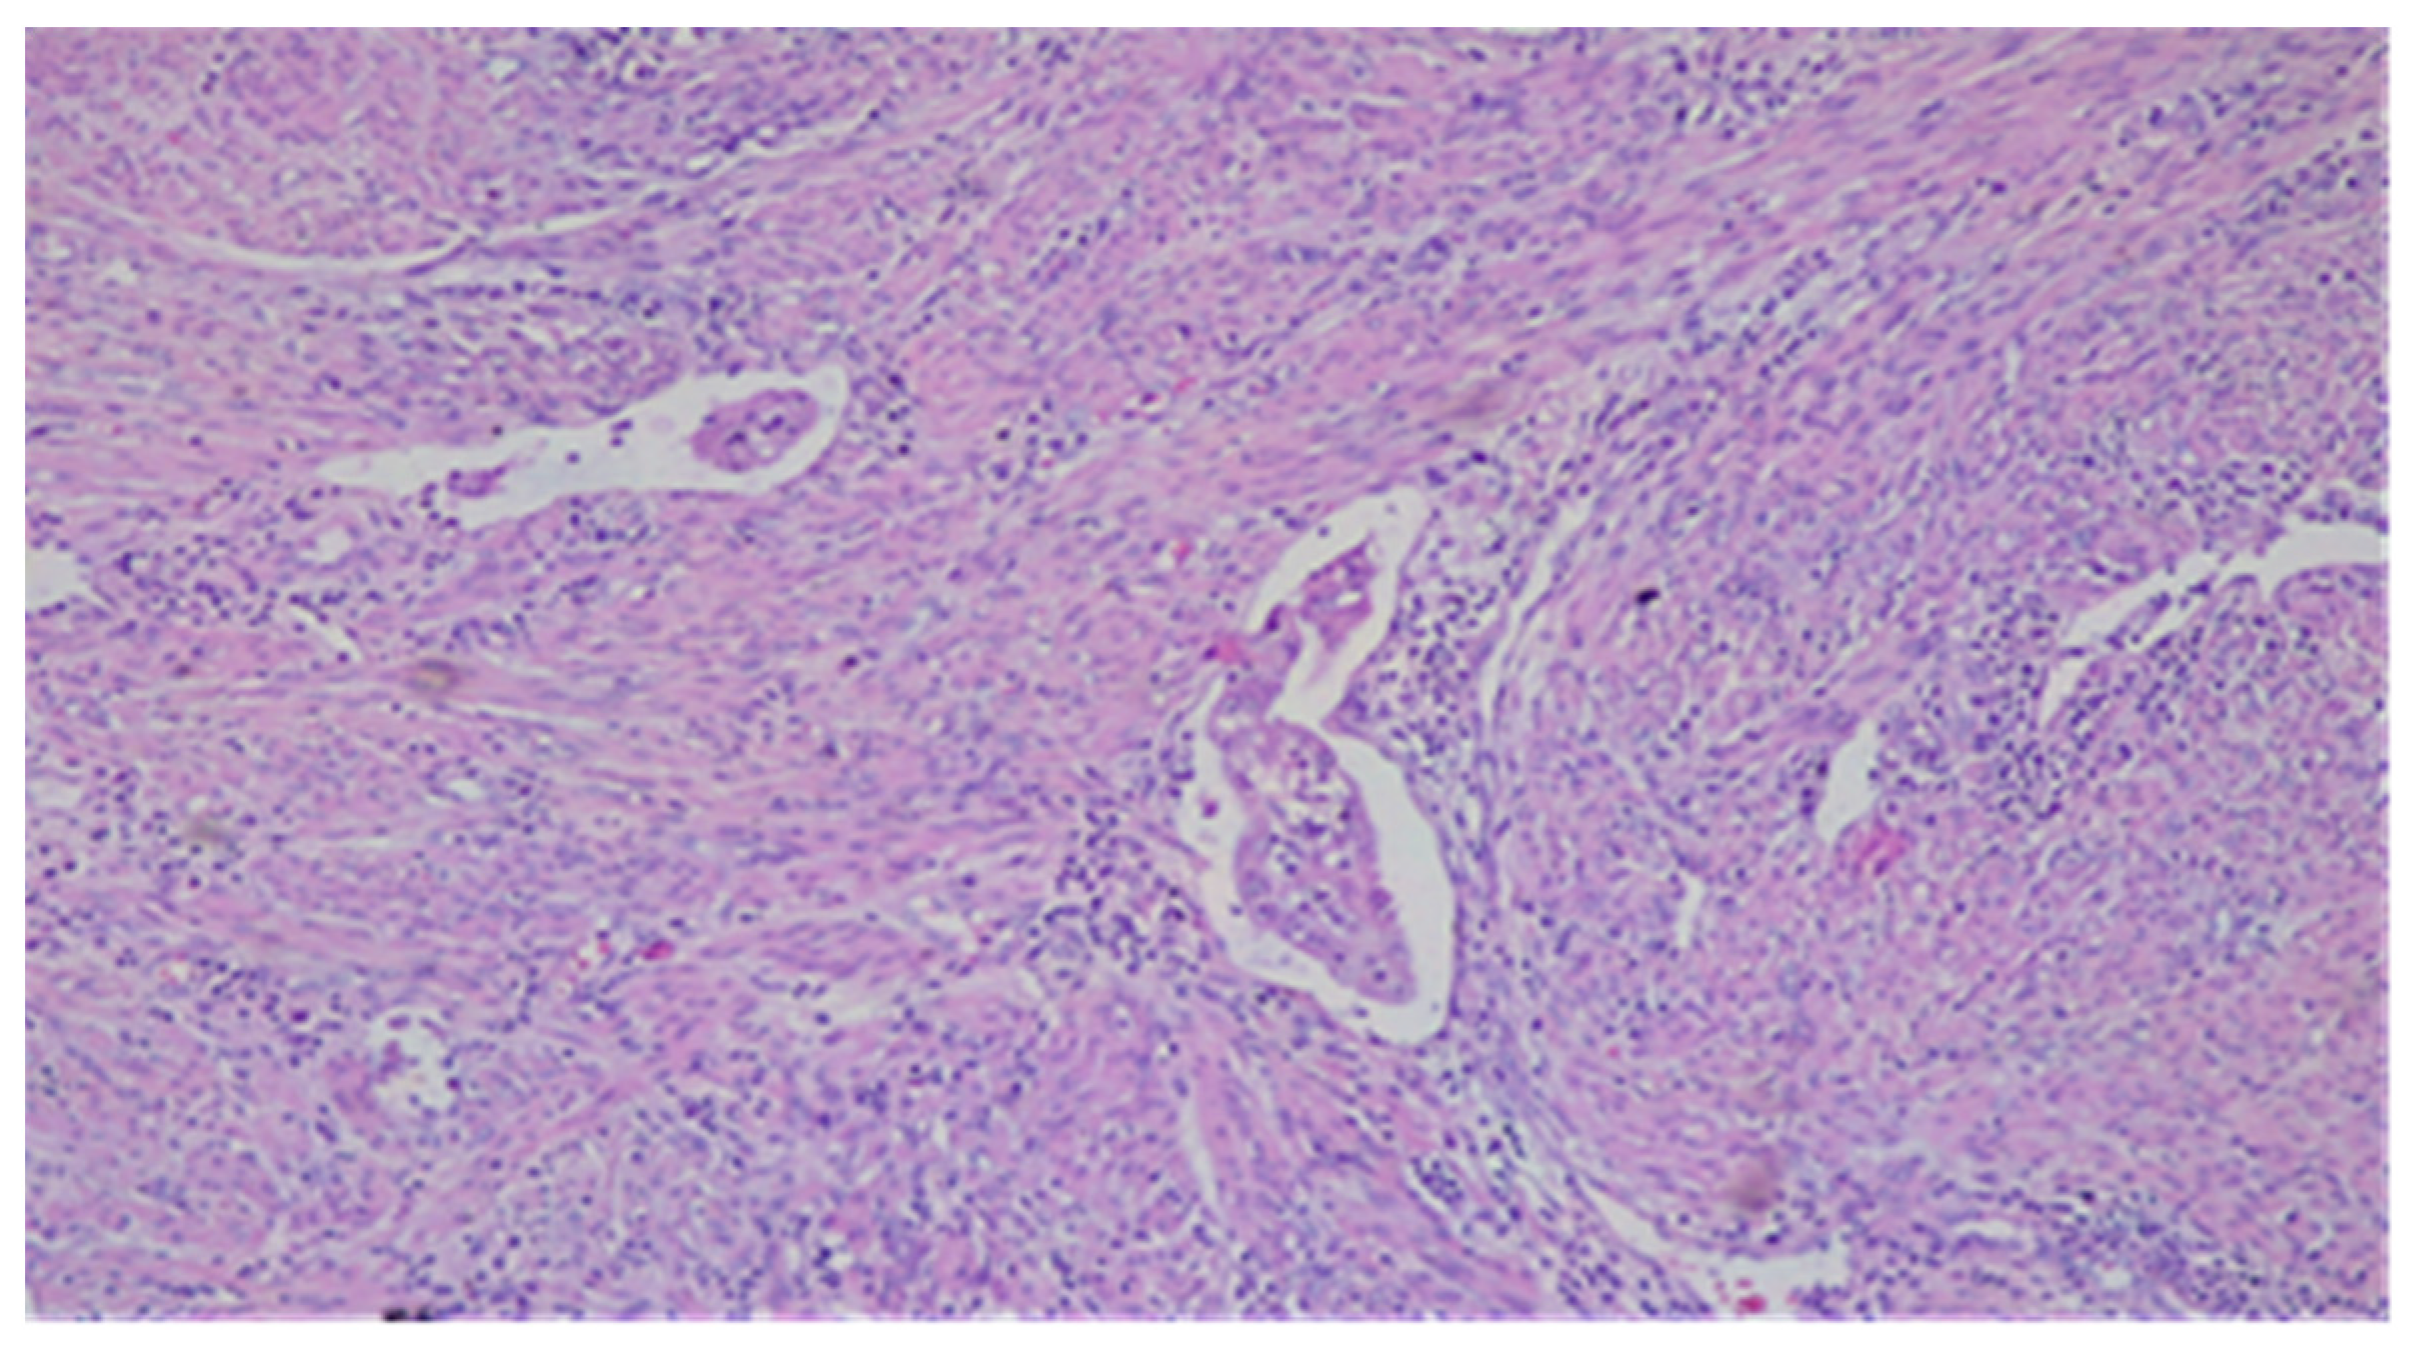

- Microcysts, lined with cells with abundant eosinophilic cytoplasm and vaguely squamoid appearance, or with flattened cells. Lumens often contain neutrophils and occasionally eosinophils.

- Elongated structures lined with the same types of cells and containing the same inflammatory cells in their lumens.

- Clusters of detached cells or individual cells lying in edematous or myxoid tissue.